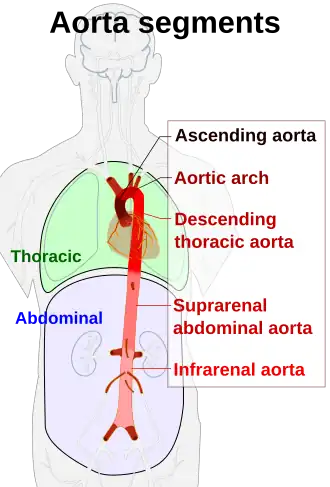

Schematic view of the aorta and its segments | |

In anatomical sources, the aorta is usually divided into sections.[2][3][4][5]

One way of classifying a part of the aorta is by anatomical compartment, where the thoracic aorta (or thoracic portion of the aorta) runs from the heart to the diaphragm. The aorta then continues downward as the abdominal aorta (or abdominal portion of the aorta) from the diaphragm to the aortic bifurcation.

Another system divides the aorta with respect to its course and the direction of blood flow. In this system, the aorta starts as the ascending aorta, travels superiorly from the heart, and then makes a hairpin turn known as the aortic arch. Following the aortic arch, the aorta then travels inferiorly as the descending aorta. The descending aorta has two parts. The aorta begins to descend in the thoracic cavity and is consequently known as the thoracic aorta. After the aorta passes through the diaphragm, it is known as the abdominal aorta. The aorta ends by dividing into two major blood vessels, the common iliac arteries and a smaller midline vessel, the median sacral artery.[6]: 18